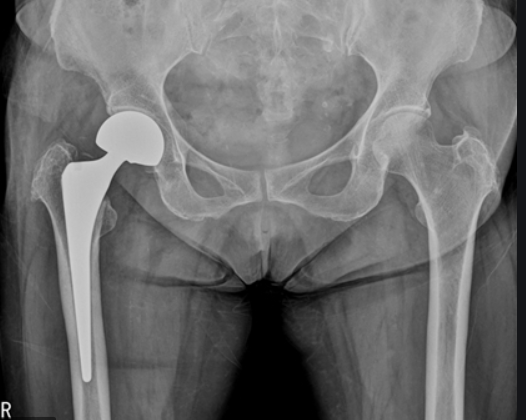

두번쨰로는 대퇴골두에만 인공뼈를 삽입하여 치환시키는 방법과 세번째로는 관절 부분 전체를 인공관절로 바꿔주는 방법이 있습니다. 이 경우에는 심하게 괴사가 된 경우에 사용하는 방법으로 합병증이 적고 기능개선이 우수하다고 알려져 있습니다.